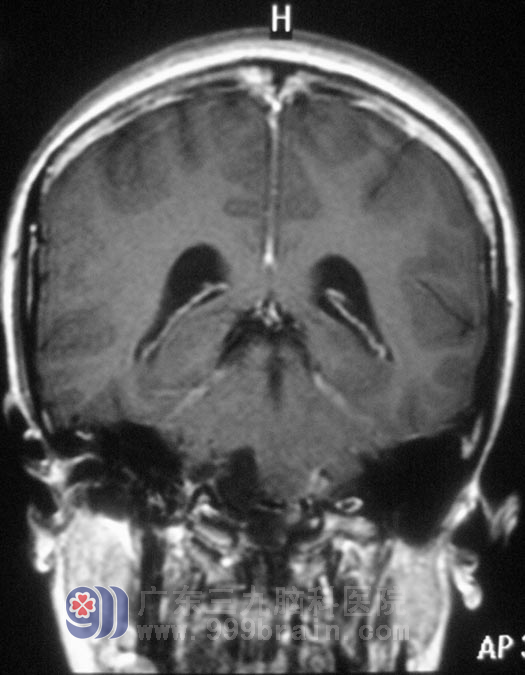

12月13日,鲁明主任主刀,在全麻下行右侧延髓腹外侧胆脂瘤切除术,作“倒L”型切口,术中见灰褐色肿瘤组织,位于右侧延髓腹外侧,质软,血供一般,在显微镜下分块切除,肿瘤基底部与副神经、舌咽神经、迷走神经粘连紧密,予镜下小心分离后切除,对副神经、舌咽神经、迷走神经、小脑后下动脉均保留完整,手术过程顺利。经过一段时间的治疗,小凤没有出现术前担心的并发症,术前症状均有所缓解。术后经病理证实为:(延髓腹外侧)胆脂瘤。